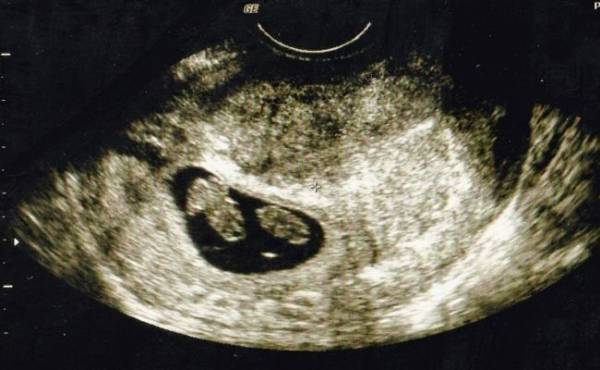

エコーで確認すると3人分の心拍が!

私が3人目を妊娠したのは長男が3歳、次男が1歳のときでした。そろそろ赤ちゃんの心拍が確認できるかな?なんて期待を胸に抱きながら、内診台でエコーを見ていると見覚えのある袋が2つ? その中には心拍のように動いて見えるのが3つ?

私が混乱していると、先生が「お母さん。赤ちゃん何人か見える?」と聞いてきました。先生と一緒に確認し、見事に3人の心拍を確認! パニックで笑うことしかできず、頭の中は真っ白で少しの間その場から動けませんでした。